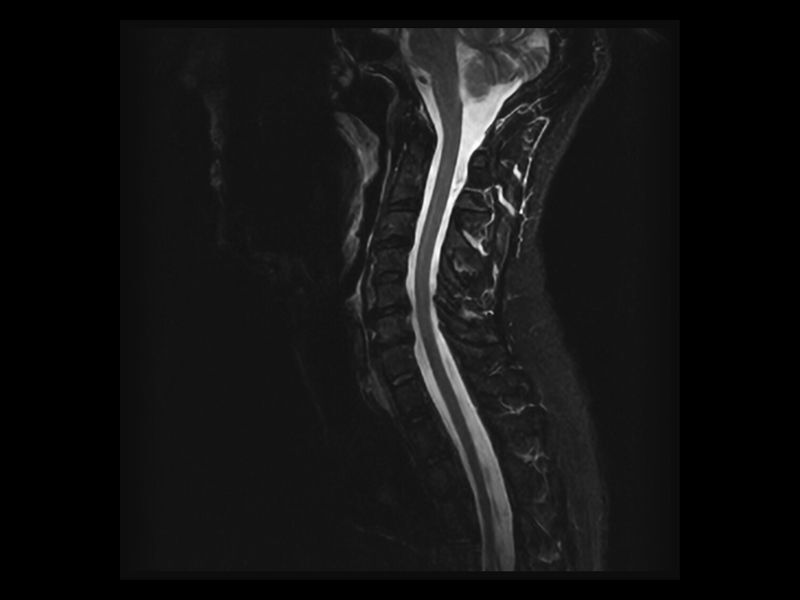

Clinical Images